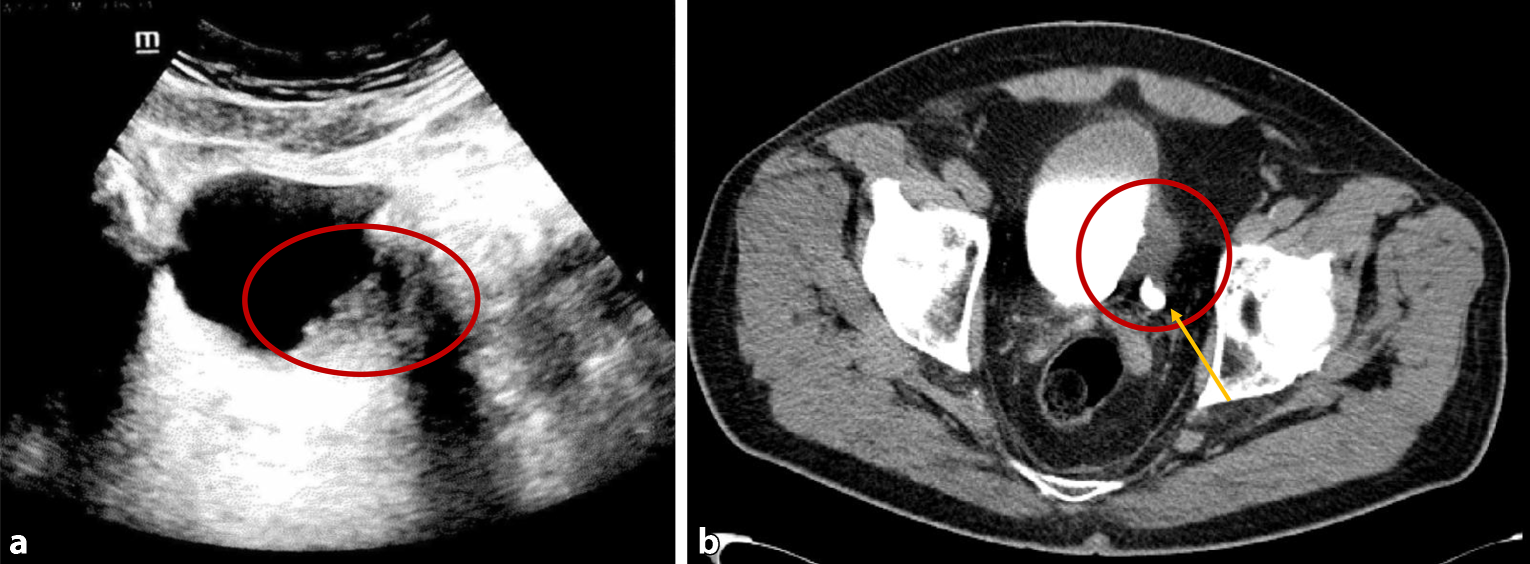

In Ihre Ambulanz kommt ein 65-jähriger Patient mit stattgehabter einmaliger und erstmaliger Makrohämaturie. Dysurische und pollakisurische Beschwerden werden verneint. Aktuell ist der Urin klar. Im Ultraschallbild sehen Sie einen ca. 3–4 cm großen Blasentumor am linken Blasenboden (Abb. 1a) und einen weiteren exphytischen Tumor am Blasendach. Zudem zeigt sich eine Grad-II-Ektasie der linken Niere. Die Laboruntersuchung ist bis auf eine Anämie (Hämoglobin- [Hb-]Wert 12,6 g/dl) unauffällig.

a Ultraschallbild der Harnblase mit Verdacht auf Harnblasentumor an der linken Trigonalleiste. b CT-Urogram des Patienten vor transurethraler Resektion von Harnblase (TURB) mit deutlicher Wandverdickung im Bereich des rechten Ostiums und erweitertem Harnleiter präostial (Pfeil)